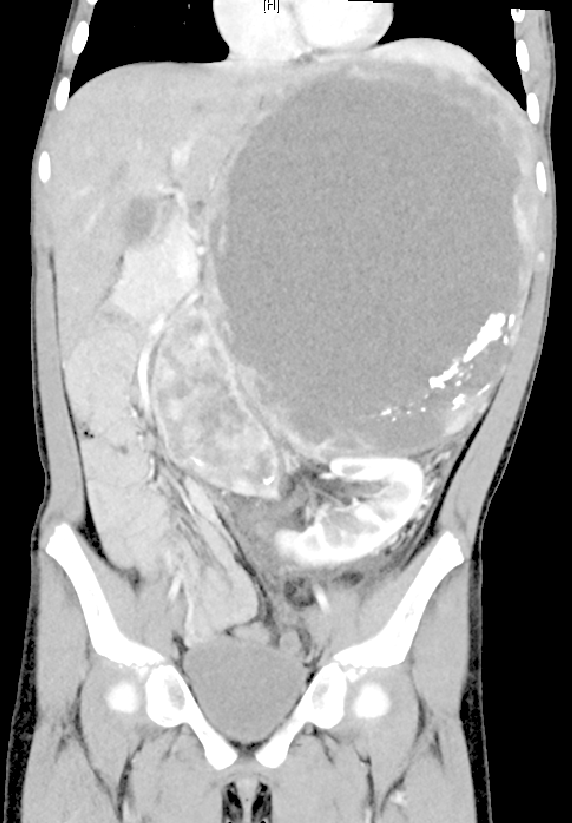

2023年年底,看到很多关于罕见病的好消息和新政策,爸爸妈妈重新鼓起勇气,而这一次,小钰的核磁检查显示:腹膜后肿块已经长到了惊人的17.6*11cm,还出现了腹膜后多发淋巴结,合并腹盆腔积液。

详尽的术前评估结果提示,小钰的情况远比之前复杂。肿瘤体积巨大,侵入血管及周围组织,切除肿瘤并保留左肾是摆在团队面前的极大挑战。

术前CT检查显示肿瘤体积巨大